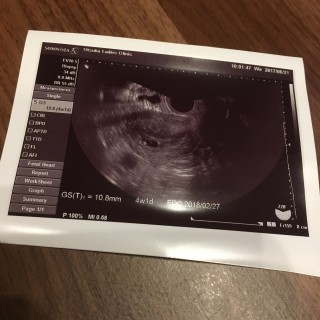

胎嚢10.8mm。 下腹部痛があるたまゆっくり休息しております。